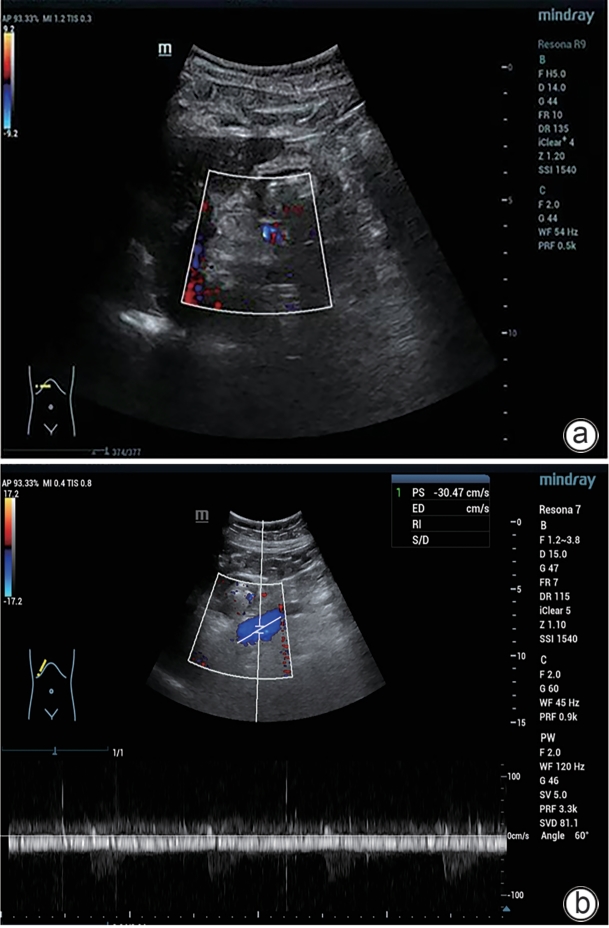

摘要: 门静脉血栓是肝硬化患者常见且严重的并发症,门静脉血流动力学的改变与门静脉血栓的发生密切相关。合并巨大的自发性脾肾分流时门静脉灌注减少、血流速度减慢,极有可能削弱门静脉血栓的抗凝效果。本文将报道1例通过栓塞自发性脾肾分流道联合抗凝治疗策略,实现了门静脉的完全再通,然而,仍需高质量的临床研究进一步验证和支持这一策略的有效性。Abstract: Portal vein thrombosis (PVT) is a common and severe complication in patients with liver cirrhosis, and alterations in portal hemodynamics are closely associated with the development of PVT. The presence of large spontaneous splenorenal shunt (SSRS) may lead to reductions in portal vein perfusion and blood flow velocity, which may compromise the anticoagulant effect on PVT. This article reports the treatment strategies of SSRS embolization combined with anticoagulant therapy that help to achieve complete recanalization of the portal vein; however, high-quality clinical studies are still needed to further validate and support the effectiveness of this strategy.